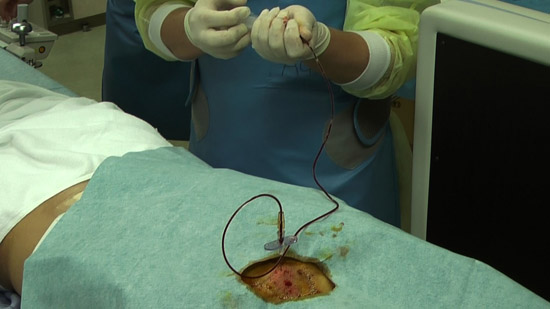

(2)Set the positioning by checking the puncture site along with the image on the radiological screen.

(3)Administer local anesthesia.

(4)Conduct an epidural puncture by the resistance loss method, checking with the image on the radioscopy screen.

※Inject the contrast medium and check it again. Capture a confirmation image at the same time.

(5)Connect an extension tube to the puncture needle and fill the autologous blood syringe with the collected blood (mixture contrast medium).

Check with the image on the radioscopy screen.

(6)Infuse the autologous blood.

While communicating with the patient, observe the patient’s condition.

Check subjective physical condition of patients after 10 cc infusion and capture a projectional image.

Successively, inject all the autologous blood.

Capture projectional images at the end of infusion.